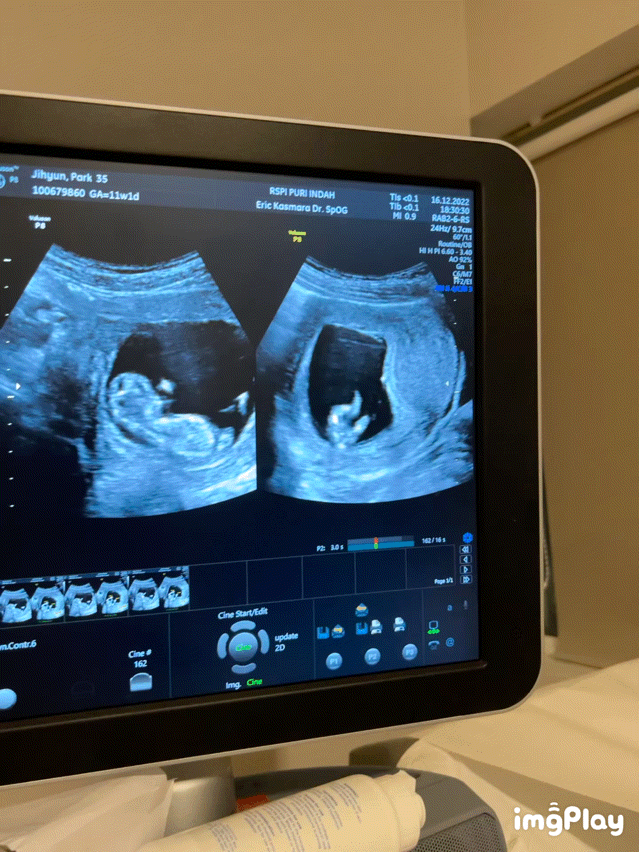

어느날 병원에서 본 초음파 영상에 명백한 아들의 상징이 찍혔다.

문자 그대로 콩알만한 녀석인데도 그 상징은 꽤나 웅장했다.

의심의 여지 없이 아들이었다.

의사의 조언 없이도 우리는 우리가 아들을 가졌다는 사실을 알게 되었다.

아내가 옳았다.

육감있는 여자다.